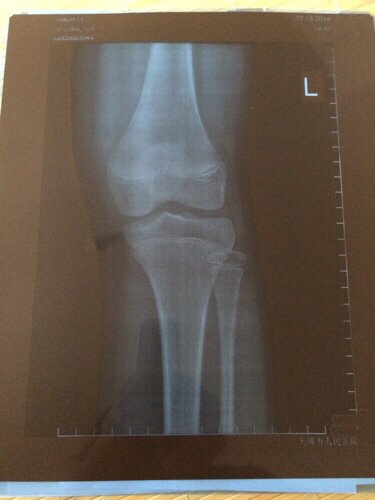

女孩来了月经还有长高的可能吗?在医院做了骨龄,有没有闭合我看不懂,请看得懂的帮我看看,看看还有没有

女孩来了月经还有长高的可能吗?在医院做了骨龄,有没有闭合我看不懂,请看得懂的帮我看看,看看还有没有长高的可能,回答好的一定采纳。         还有就是月经来了还有多少公分长的可能。

没愈合可以长个